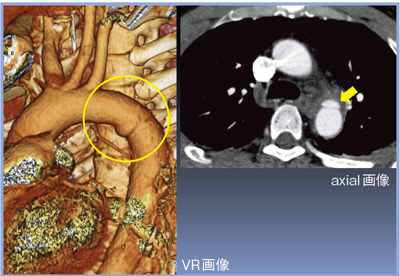

1mm厚の再構成画像では,axial画像で右側頭葉の脳挫傷,左頭頂葉のクモ膜下出血,VR画像で左浅側頭動脈の損傷を認めた(図1)。

1mm×40の撮影条件でも,胸部大動脈損傷が明瞭に描出された(図2)。見落としを防ぐためには,いかに速くワークステーションで画像を確認できるかが重要であり,再構成時間の高速化のメリットは大きい。

![]() 図1 症例1:1mmスライス厚の再構成画像 ←左浅側頭動脈の損傷 |

![]() 図2 症例1:胸部大動脈損傷(峡部) |